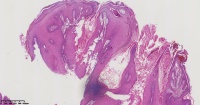

角化棘皮瘤?

性别

男

年龄

45岁

临床诊断

一般病史

面部包块

标本名称

图3

倾向脂溢性角化病。